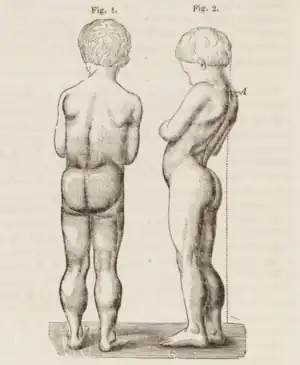

A classic sign of DMD is trouble getting up from lying or sitting position,[9] as manifested by a positive Gowers' sign. When a child tries to arise from lying on his stomach, he compensates for pelvic muscle weakness through use of the upper extremities:[7] first by rising to stand on his arms and knees, and then "walking" his hands up his legs to stand upright. Another characteristic sign of DMD is pseudohypertrophy (enlarging) of the muscles of the tongue, calves, buttocks, and shoulders (around age 4 or 5). The muscle tissue is eventually replaced by fat and connective tissue, hence the term pseudohypertrophy. Muscle fiber deformities and muscle contractures of Achilles tendon and hamstrings can occur, which impair functionality because the muscle fibers shorten and fibrose in connective tissue. Skeletal deformities can occur, such as lumbar hyperlordosis, scoliosis, anterior pelvic tilt, and chest deformities. Lumbar hyperlordosis is thought to be compensatory mechanism in response to gluteal and quadricep muscle weakness, all of which cause altered posture and gait (eg: restricted hip extension).[11][12]

The disease was first described by the Neapolitan physician Giovanni Semmola in 1834 and Gaetano Conte in 1836.[42][43][44] However, DMD is named after the French neurologist Guillaume-Benjamin-Amand Duchenne (1806–1875), who in the 1861 edition of his book Paraplegie hypertrophique de l'enfance de cause cerebrale, described and detailed the case of a boy who had this condition. A year later, he presented photos of his patient in his Album de photographies pathologiques. In 1868, he gave an account of 13 other affected children. Duchenne was the first to do a biopsy to obtain tissue from a living patient for microscopic examination.[45][46]